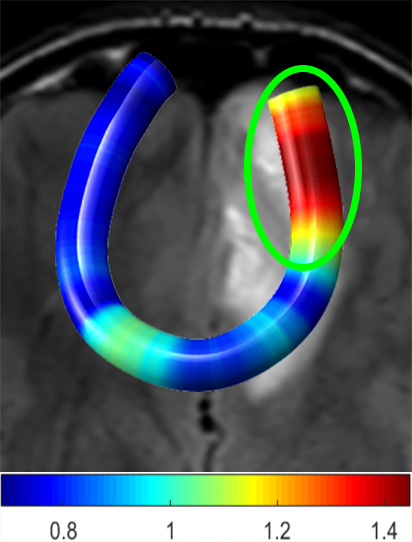

We performed pairwise comparison between two scans of a 32-year-old basketball player, diagnosed with mild occipital traumatic brain injury and frontal hemorrhage due to contrecoup impact, acquired one week and 6 months post-injury. The hemorrhagic lesion at the frontal right hemisphere of the player is no longer visible in the FLAIR image acquired 6 months after injury (Fig. 2a). Local differences between corresponding, longitudinal FA- and MD-FFDD profiles of the FMT (chosen due to its proximity to the lesion area) are shown in Fig. 2d. Figs. 2b-c present color-coded FMT to visually demonstrate these differences. Results show significant longitudinal variability at the right hemisphere part of the tract, corresponding to the lesion area, and relatively minor differences along the rest of the tract. These results should be considered as a proof of concept, validating the FFDD analysis results for the detection and localization of mTBI-related variabilities between fiber bundles.

| (a) FLAIR | (b) FA-FFDD | (c) MD-FFDD | (d) Local Differences |

MD-FFDD |